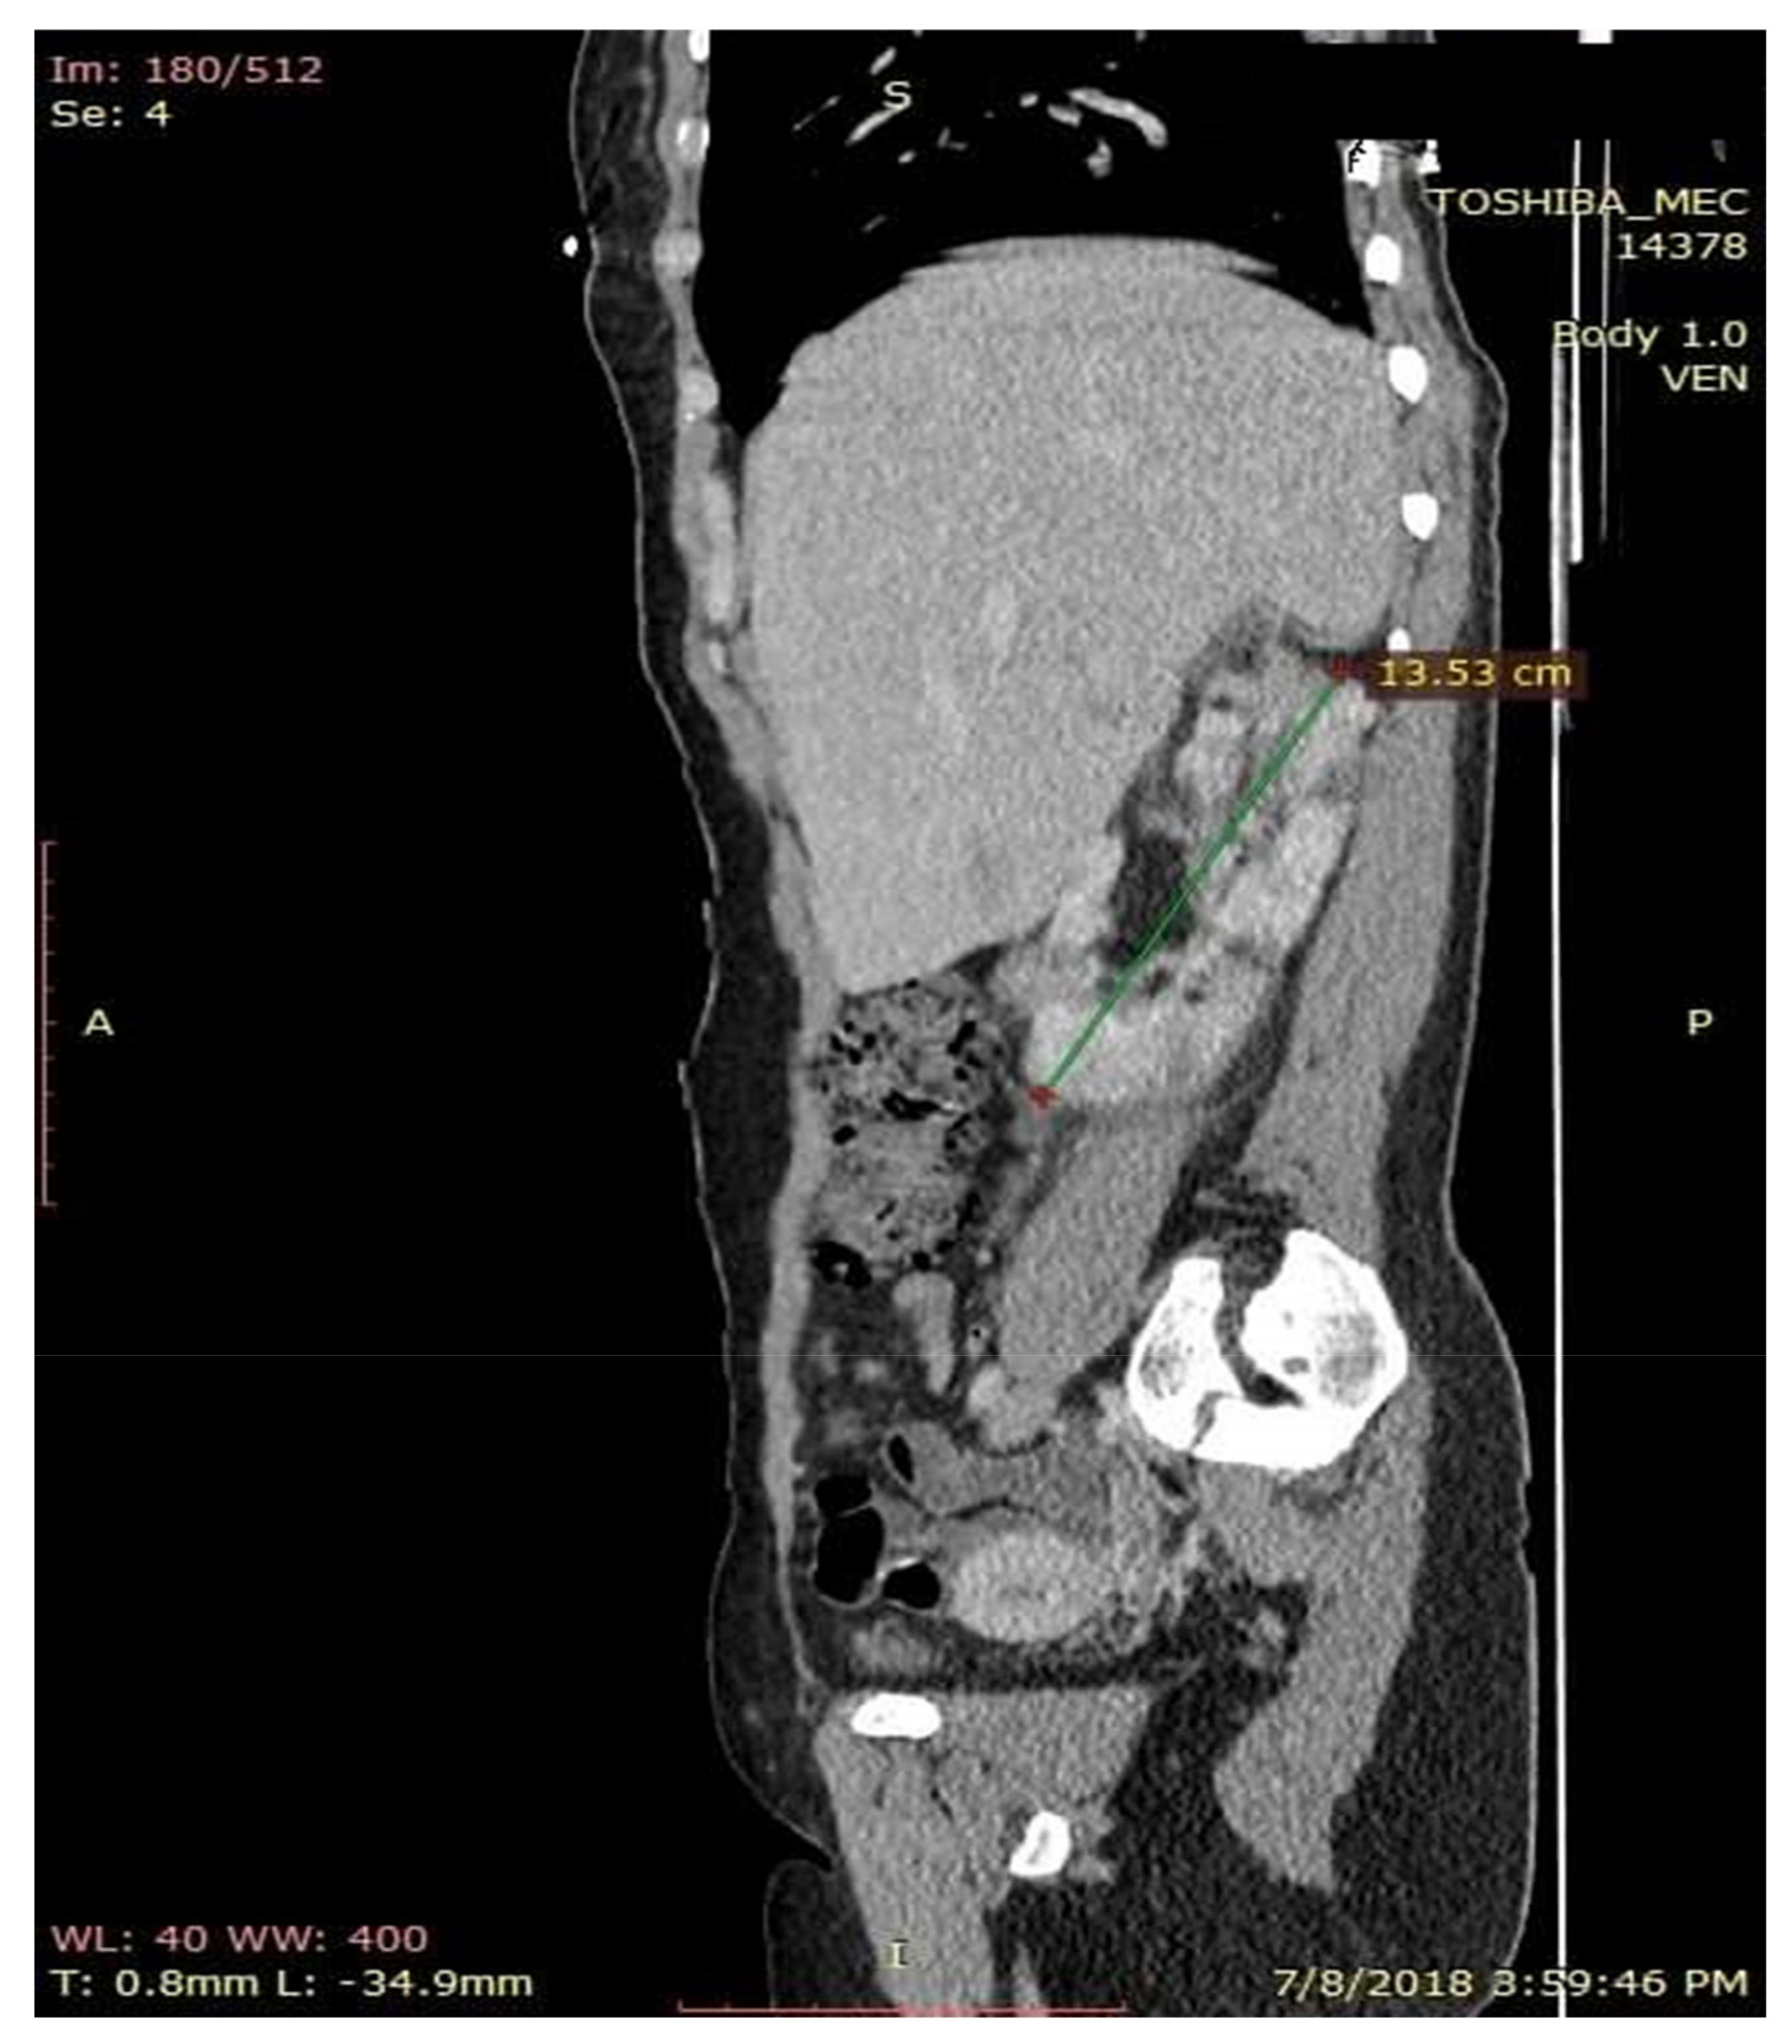

Figure 6.

CT aspect of kidney modifications. Sagital CT section with contrast substance.

The chest X-ray results were normal, but the computer tomography (CT) scan of the abdomen and pelvis evidenced irregular kidney contour layout, undifferentiated images between cortical and medullar structures, with non-homogenous round components, suggestive of bilateral kidney angiomyolipomas, renal cortical retention cysts (with diameters between 3–16 mm), with dilatatory secretion in the right side and conserved secretion and excretion on the left side. Images of a lithiasic component were also found on the middle right caliceal branches (size of 7.1/6.5 mm) and one of the left side with a smaller dimension, 2.5/2.5 mm (Figure 5, Figure 6 and Figure 7). Similarly, the computer tomography scan of the abdomen and pelvis showed bilateral inflammatory infiltration in soft tissue surrounding the kidney and the entire surface of the ureters, as well as a small quantity of fluid in the right perirenal area—suggestive of pyelonephritis, periurethritis and angiomyolipomatosis. The computer tomography scan of the abdomen and pelvis revealed subcentimeter periaortic and intraortocaval lymph nodes. Moreover, the CT changes were represented by the evidence of the osteolytic lesions in the thoraco-lumbar and pelvic bones. The CT scan of the skull revealed the following changes: a subependymal giant cell astrocytoma (SEGA), with incipient hydrocephalus in the left lateral ventricle.